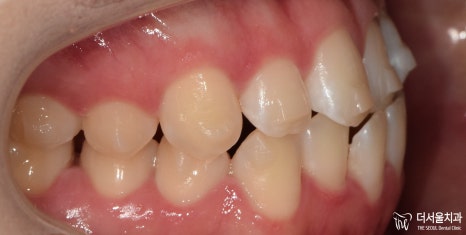

『인비절라인 기간 ’10개월’간의 기록 (치료 마무리)』

다행히 꾸준히 착용을 잘 해주신 덕에

10개월 만에

치료를 마무리할 수 있었습니다.

1) 반대교합 개선

2) 정중선 일치

3) 악궁 (U-shape)

4) 돌출 해소

모든 문제들이 해결이 되었군요.